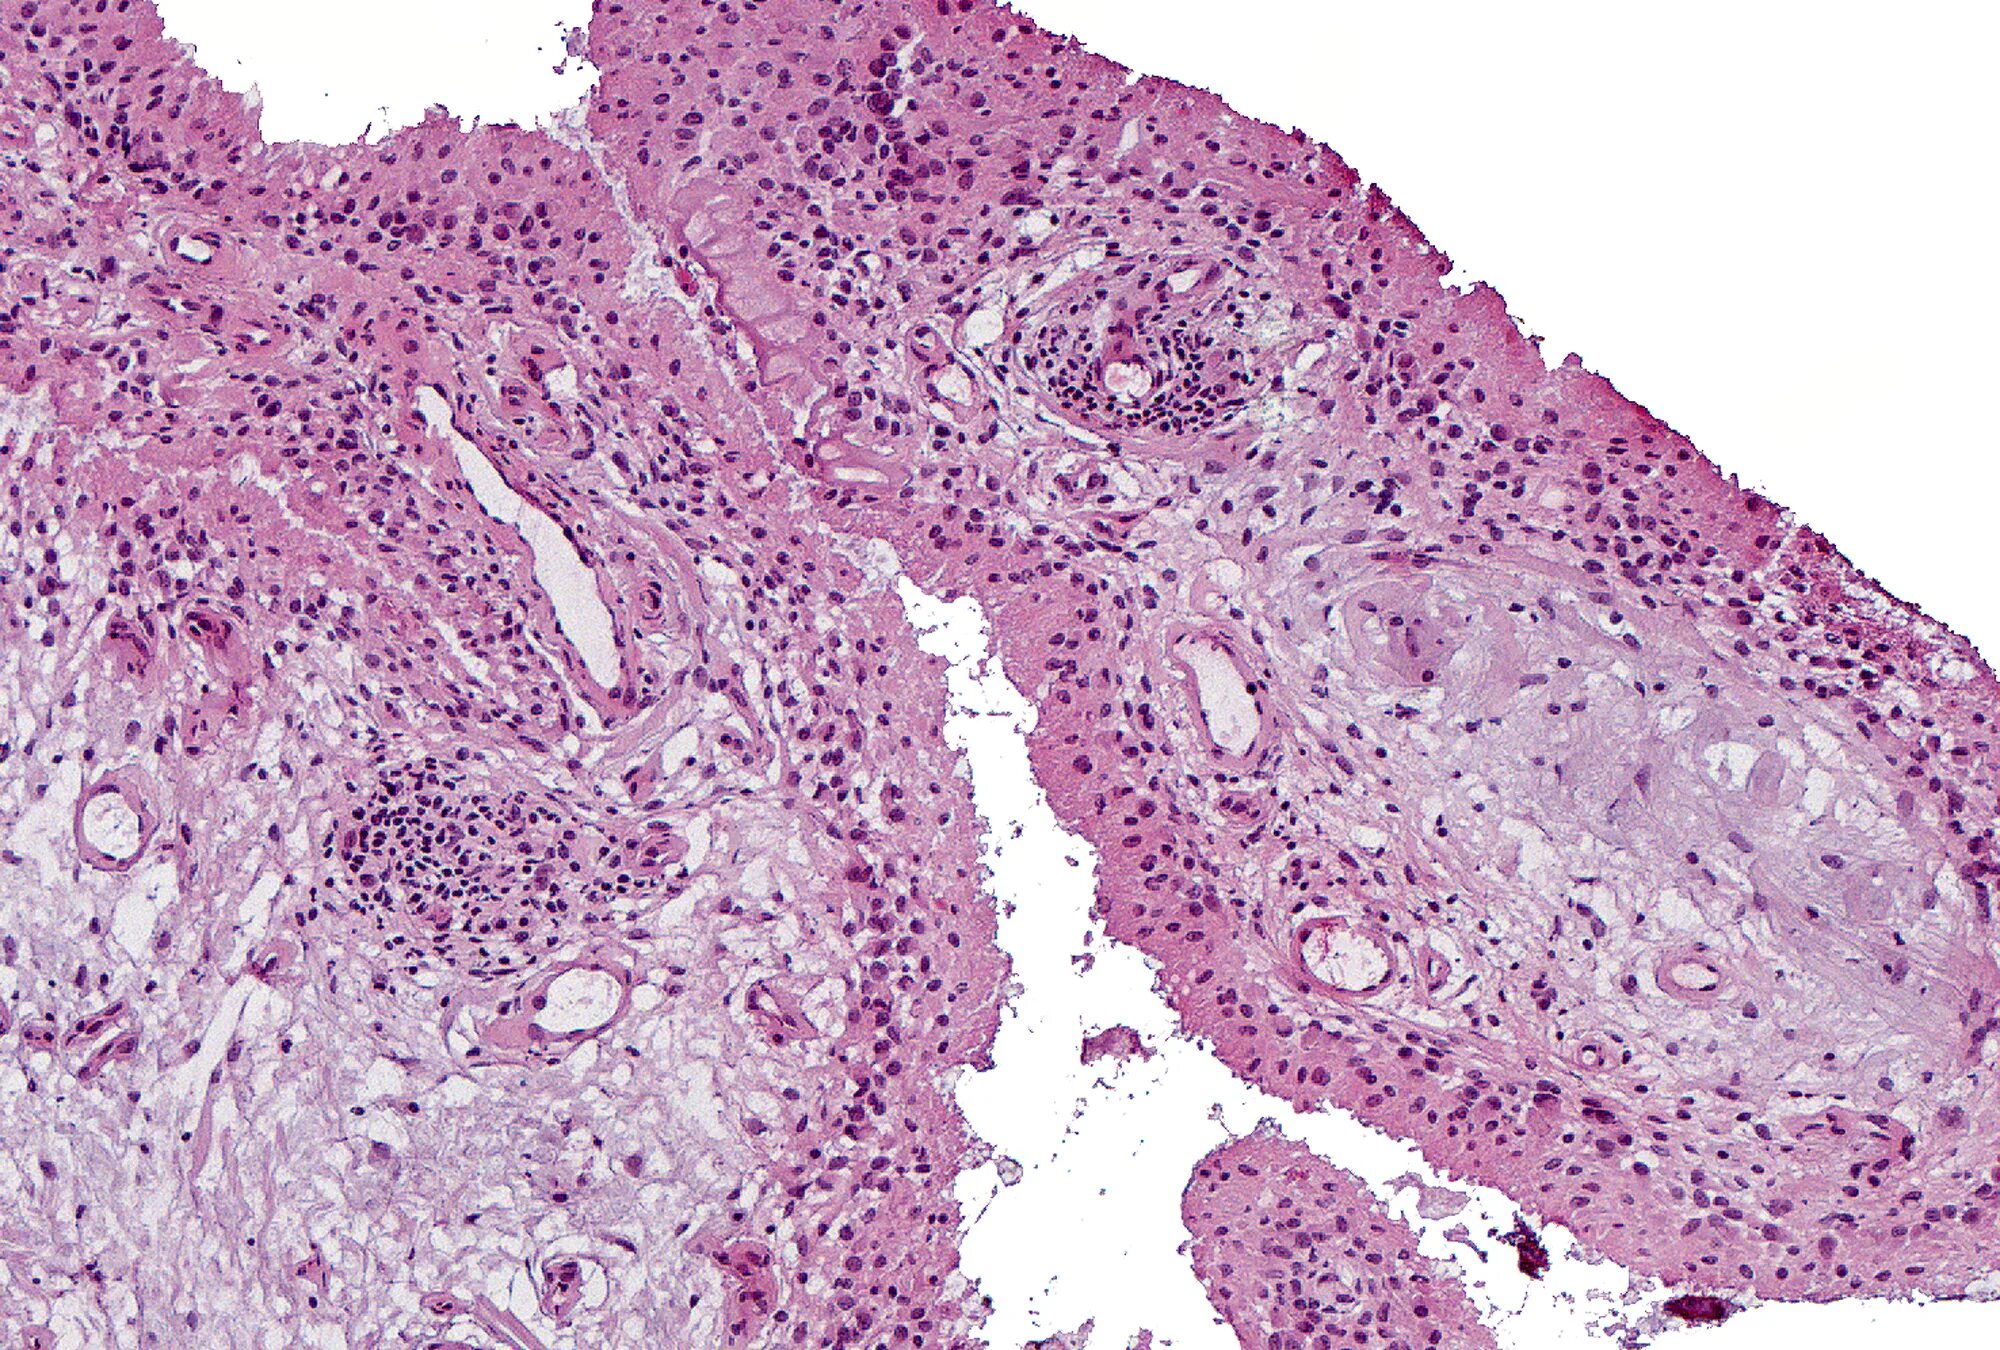

Д гистология